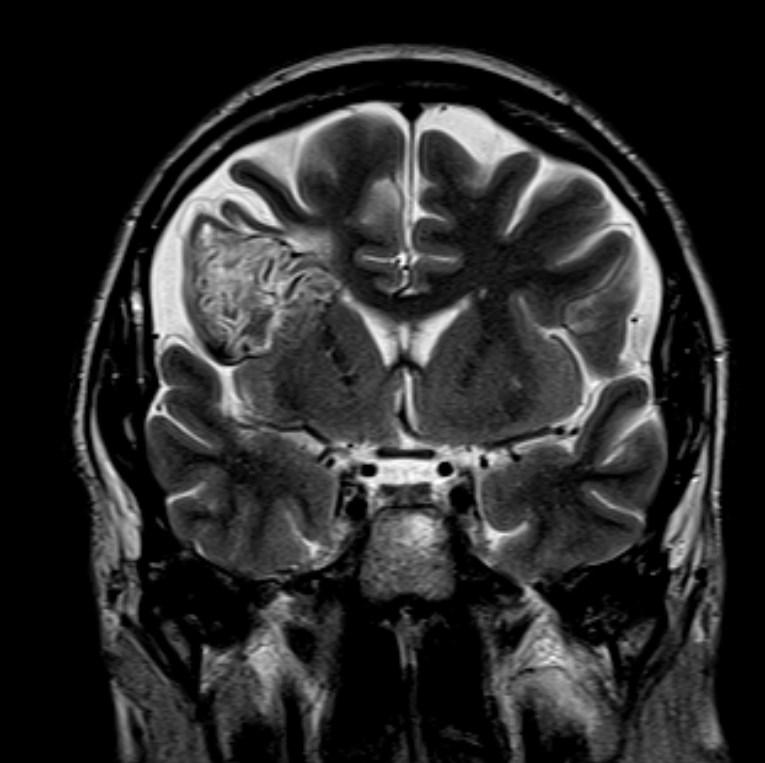

Answer: Primary hydatid cyst of right frontal lobe.

MR images revealed Gharbi type V hydatid cysts in right frontal lobe.

Gharbi classified hydatid cyst ultrasonographic images into 5 types: Type 1, walled, unilocular, anechoic; type 2, separated membranes; type 3, multisepta, daughter vesicles; type 4, heterogenic, hypo-hyperechogenic; type 5, calcification of a section of the wall or completely calcified (4). The cysts characteristically have three components: Pericyst, Exocyst, and Endocyst.